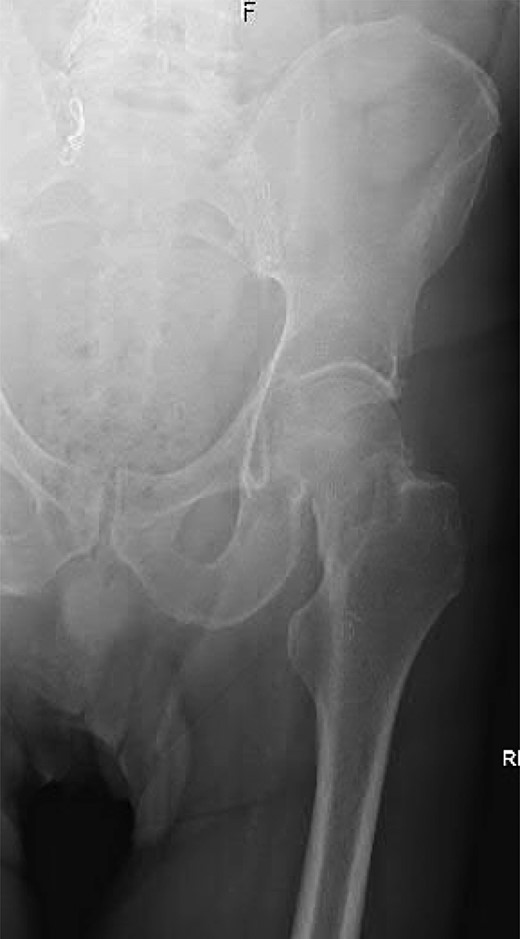

A 74-year-old male was admitted with an intracapsular fractured left neck of femur (Fig. 1). According to the NICE guidelines, he received a cemented THR (Fig. 2) via the posterior approach in the lateral decubitus position. Five weeks prior, he had an EVAR for a leaking AAA. Due to a calcified, narrow right common iliac artery (CIA), the EVAR consisted of a left aortouniiliac endograft with coil embolization of the right CIA and a femoro-femoral crossover graft (Figs 3 and 4).

Lateral radiograph of the lumbar spine demonstrating the aortouniiliac EVAR with coil embolization of the right CIA.